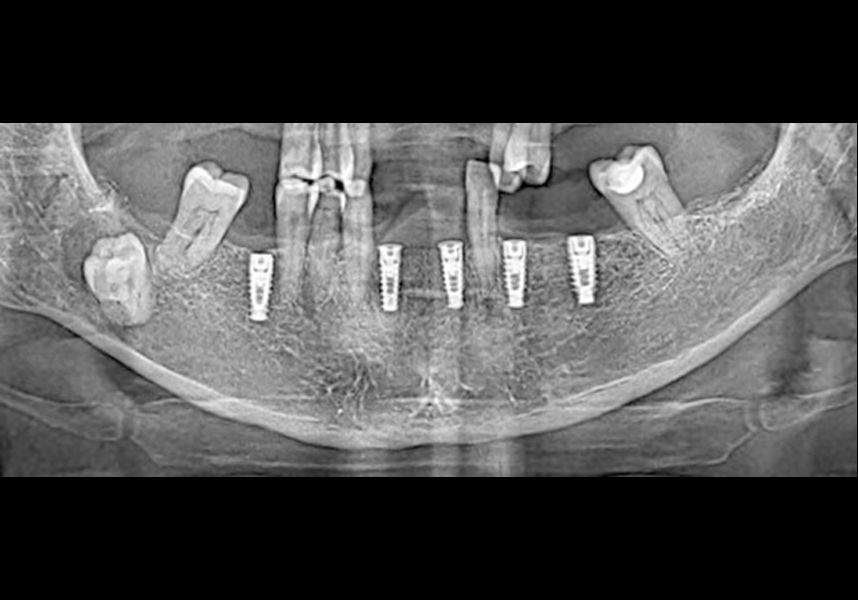

Placement of two dental implants was considered in the anteroinferior area, with simultaneous guided bone regeneration during the same surgery and the subsequent delayed placement of a metal-ceramic bridge for four teeth from 42 to 32. In addition, it was planned to insert three implants in positions 46, 34 and 36, also for restoration with metal-ceramic prosthesis.

The patient was anesthetized and a flap was made from the distal area of tooth 43 up to 36. Then two Avinent Biomimetic Ocean IC implants of 3.5x10 were inserted in positions 32 and 42.

In the posterior sector three Biomimetic Ocean IC implants of 4.0x10 were inserted in positions 36, 34 and 46 with delayed load. A small regeneration was also carried out with autologous bone in the implant in position 34, where there was no exposure, but the vestibular cortical was very fine after implant insertion.

After a post-operative period without complications, the healing abutments were fitted in a second surgical stage 5 months later. Six months after implant placement, the final metal-ceramic prosthetic restoration was loaded.